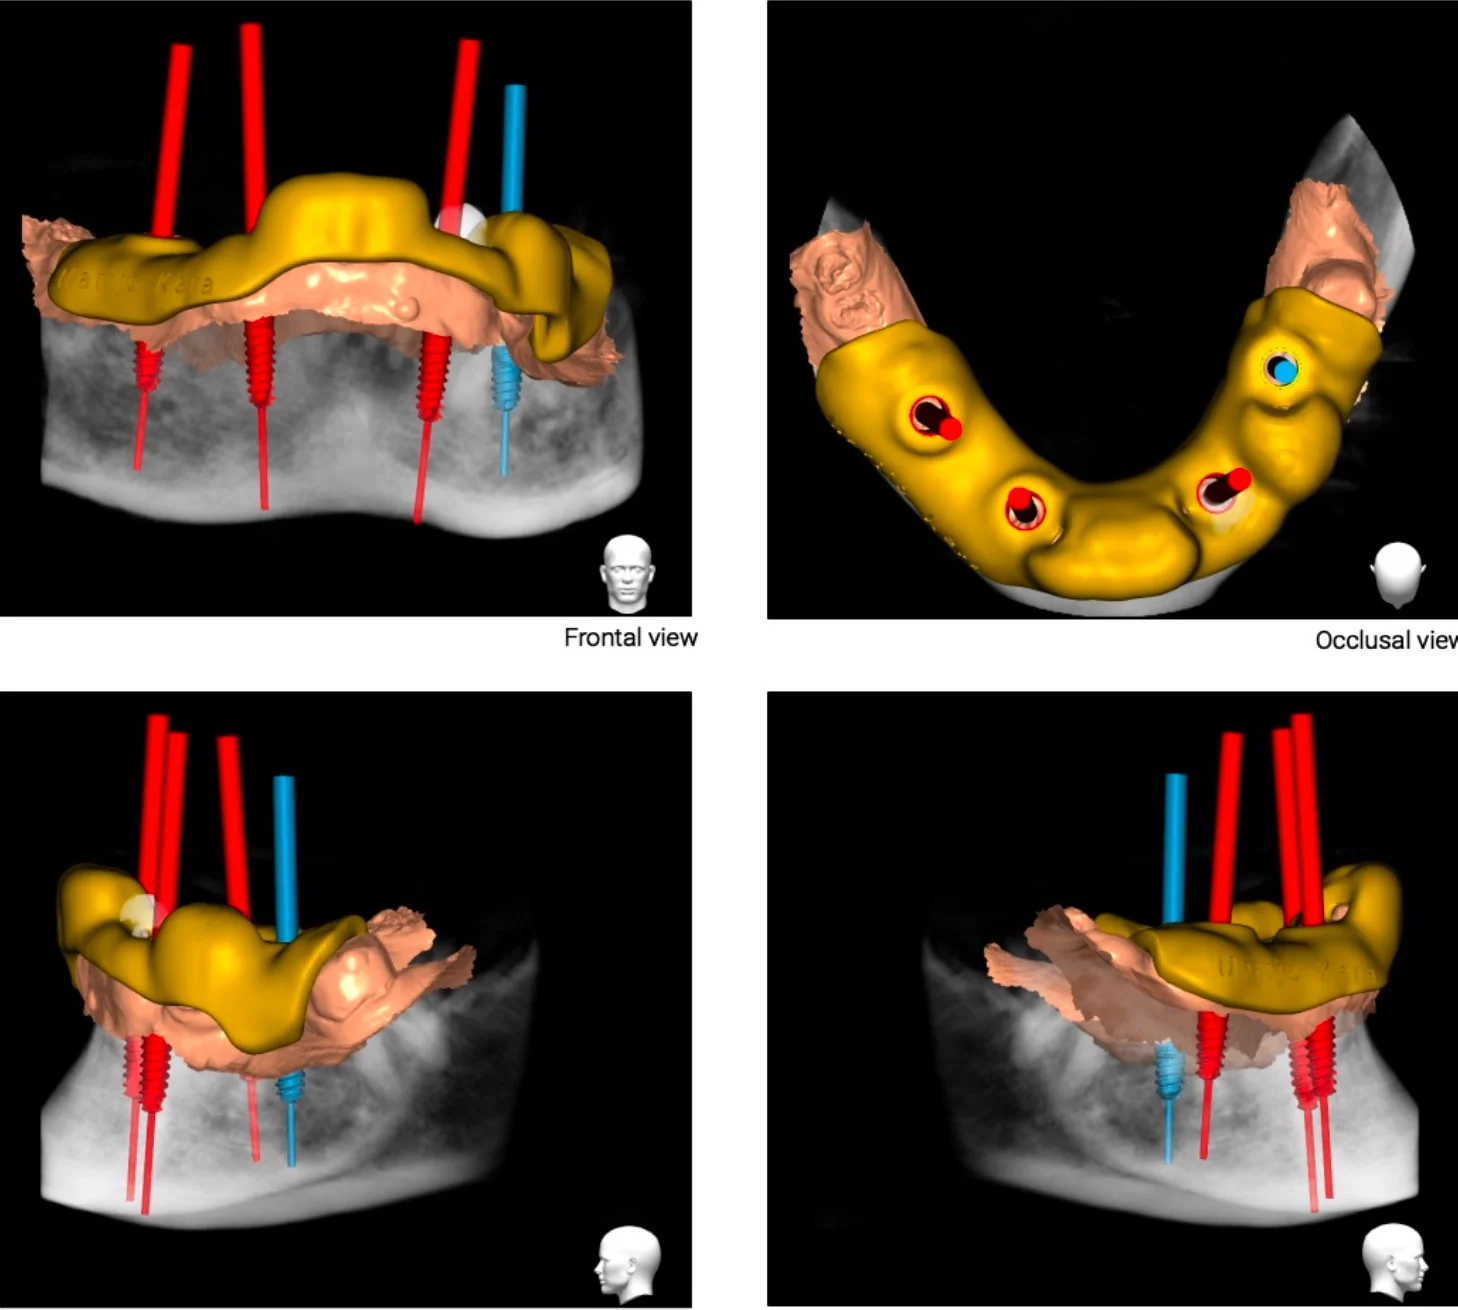

Apex Dental koristi najsuvremeniji CBCT uređaj koji daje kristalno čiste 3D presjeke svih struktura u cjelini te je moguće segmentirati regije interesa te isprintati na 3d printeru. Na taj način Vaš stomatolog može bolje upoznati Vašu anatomiju te samim time puno sigurnije izvesti operaciju ugradnje zubnih implantata što je velika prednost i za doktora i za pacijenta. 3D snimanje preduvjet je i za digitalno 3d planiranje ugradnje zubnih implantata u specijaliziranim softverima za planiranje.

• sigurnije planiranje implantata

• točna analiza gustoće kosti

• pregled teško dostupnih kanala

• procjena stanja sinusne membrane

• analiza patoloških promjena

• segmentacija anatomskih struktura i isporuka datoteka za 3d print

• izrada kirurških vodilica za ugradnju zubnih implantata

kompjutersko planiranje dentalnih implantata

#surgicalguidedesign #apexguides

Budućnost je stigla u Apex Dental Zadar

Vrhunski 3d CBCT temelj je kompjuterski vođene implantologije. Kompjuterski vođena implantologija dobitak je kako za svakog pacijenta tako i za svakog doktora dentalne medicine!